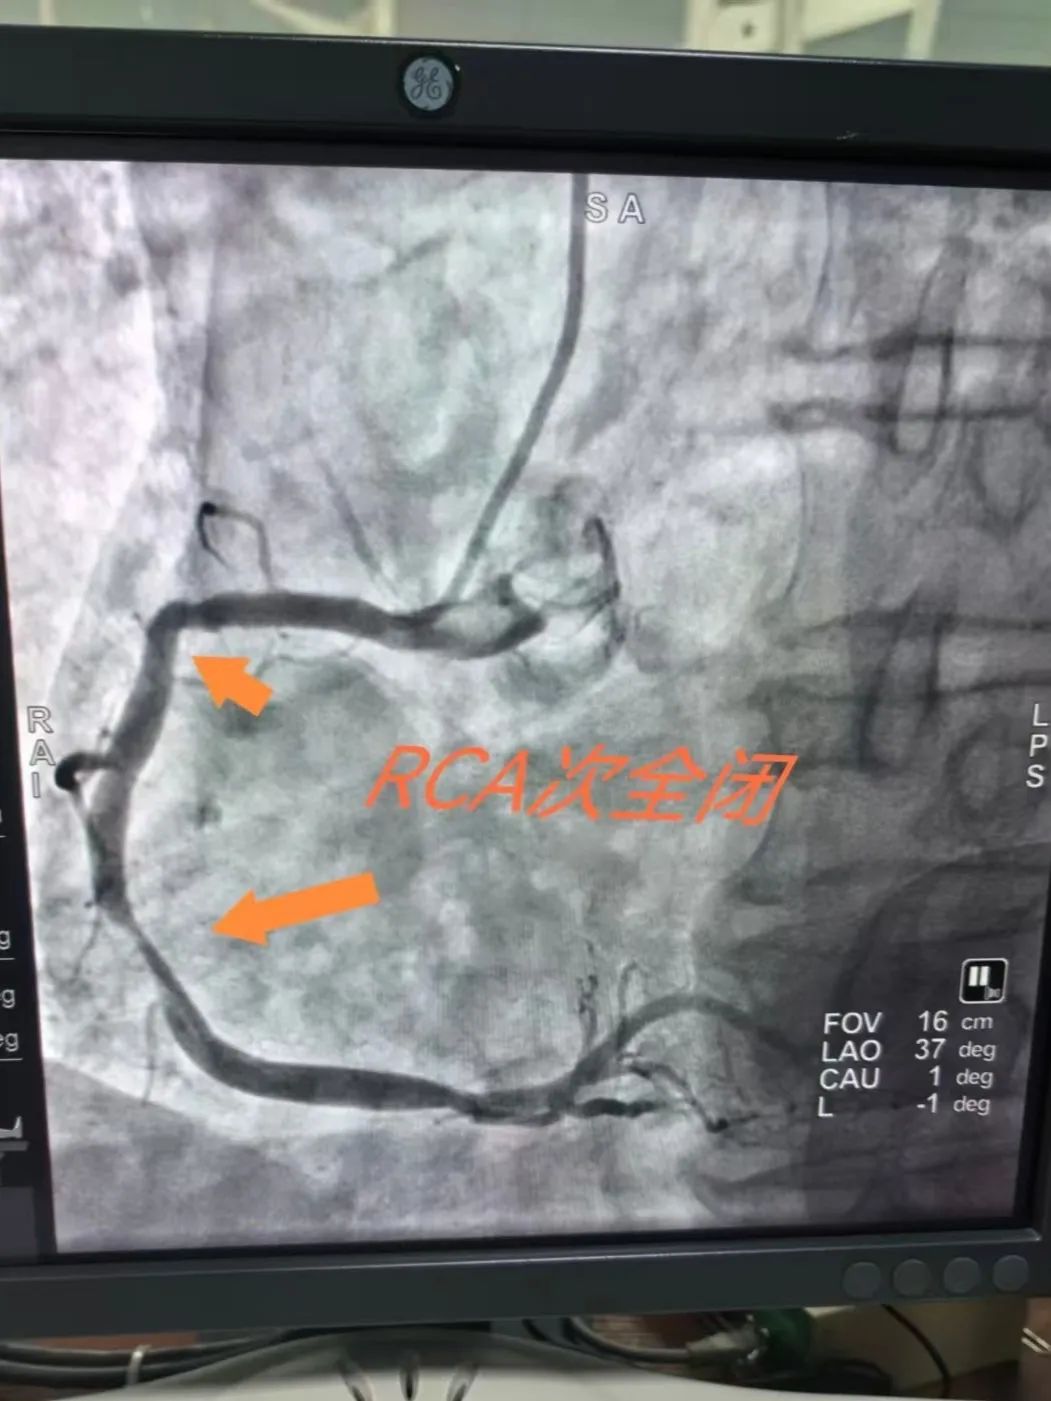

在转运途中,训练有素的急救团队已开始争分夺秒的术前准备:转运途中给予「心梗一包药」、注射肝素抗凝、建立静脉通路、抽取血标本······所有操作精准到位,为后续治疗赢得先机。7 时 56 分,救护车抵达医院,直接驶向早已准备就绪的导管室。胸痛团队医护配合默契,手术流程行云流水,8 时 22 分,导丝通过闭塞的血管,之后成功开通——从入院到导丝通过时间(DTW 时间),仅用 26 分钟!